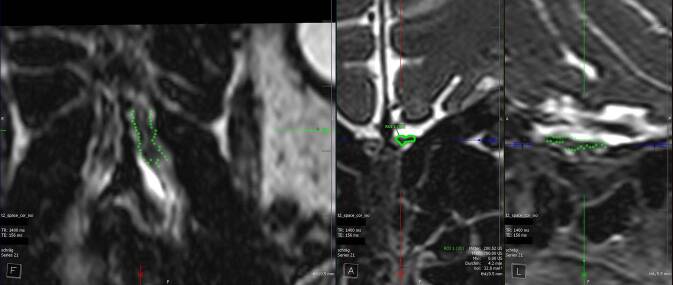

嗅觉障碍是耳鼻喉科评估的常见原因。特别是当主观和/或客观嗅觉测量的结果不确定时,需要额外的客观发现来验证嗅觉障碍。根据实际经验,并考虑到目前的文献,这篇文章的目的是作为辅助准备补充放射学报告。除了详细的病史和既往发现(如果适用)外,还应强调综合最新标准影像学的重要性,包括嗅球体积测定。除了与嗅觉有关的解剖结构的改变的文献,这支持了报道的嗅觉障碍,特殊的嗅球可视化神经放射学检查序列,包括体积测量,可以为评估有时仅主观存在的嗅觉障碍提供客观成分。在大多数情况下,没有有效的比较体积可以从可能预先存在的影像学研究中得出。因此,与嗅球参考值进行比较,在研究中确定了假定的病因和由嗅测法报告/确定的疾病程度,这是将嗅球体积与报告和/或由嗅测法确定的嗅觉功能保持几乎客观关系的唯一方法。

Disorders of olfaction are a frequent reason for an assessment in otorhinolaryngology. Particularly when the results of subjective and/or objective olfactometry are inconclusive, additional objective findings are required to verify disorders of the sense of smell. Based on practical experience and considering the current literature, this article is intended as an aid in the preparation of supplementary radiological reports. The importance of comprehensive up to date standard imaging including olfactory bulb volumetry in addition to a detailed medical history and, if applicable, previous findings should be emphasized. In addition to the documentation of alterations in the anatomical structures involved in olfaction, which support the reported disorders in the sense of smell, special neuroradiological examination sequences for the visualization of the olfactory bulb, including a volumetric measurement of the same, can provide an objective component for the assessment of sometimes only subjectively existing disorders of the sense of smell. In the majority of cases no valid comparative volumetry can be derived from a possibly pre-existing imaging study. Therefore, a comparison with olfactory bulb reference values, determined in studies for the presumed etiology and the extent of the disorder reported/determined by olfactometry is the only way to put the olfactory bulb volume in an almost objective relationship to the function of the sense of smell reported and/or determined by olfactometry.